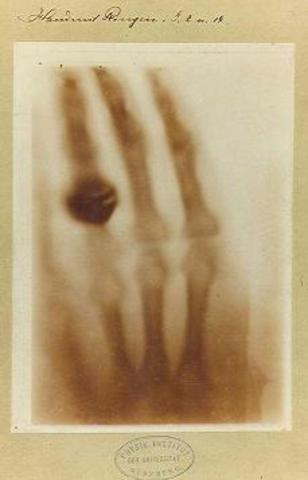

• rayos X

rayos X

descubierto de forma accidental por W.C Roentency, se trata de una radiacion electromagnetica que sirven para ver los huesos de los cuerpos.

En este periodo se realizan importantes avances en la medicina como la Penicilian que gracias a Fleming desde ese momento se pudo manejar el proceso de infecciones; gracias a los RX se ha podico realizar mejores observaciones del interior del ser humano sobre todo a nivel oseo; con el imlate del marcapaso se incia un acelerado avance cientifico que permite unir la medicina, fisica, electronica y otras para mejorar las condicones de ciertos organos que fallan en el interior del ser humano.